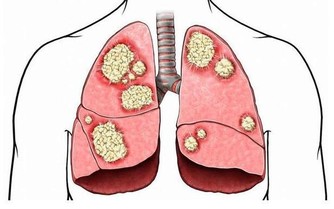

後半夜(3:00~7:00)不睡,NK細胞的活性同樣下降。NK細胞是人體免疫系統裡抗腫瘤、抗病毒的“特種部隊”,它的活性下降了,我們的免疫系統便不再強悍,癌細胞也就有了可乘之機。

此外,缺乏睡眠會導致血壓上升、內分泌和代謝異常、炎症反應炎症物質增多。在之前的課程裡我們已經講解了炎症物質與癌症的關係,過量生產的炎症物質積蓄在體內會誘發、加重癌細胞的生長與擴散,這也是睡眠不足容易引發癌症的原因之一。